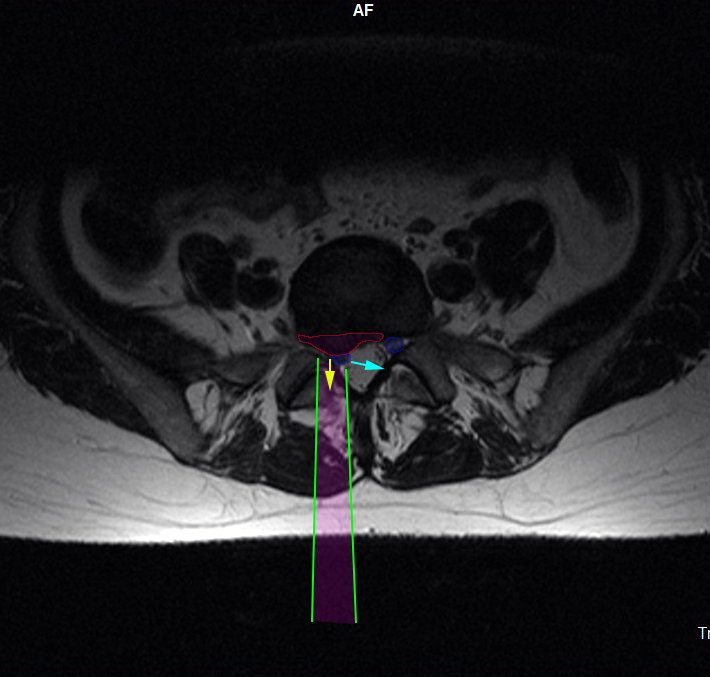

Η προσπέλαση (πράσινες γραμμές) της οσφυϊκής μικροχειρουργικής δισκεκτομής γίνεται με μικρή αποκόλληση των μυών της σπονδυλικής στήλης, διάνοιξη θυρίδας (οπής) στους συνδέσμους που καλύπτουν το νεύρο και σε ελάχιστο τμήμα του οσφυϊκού πετάλου. Το οσφυϊκό νεύρο (μπλέ) παρεκτοπίζεται και η κήλη (φούξια) αφαιρείται (κίτρινο βέλος). Όταν χρειάζεται, και από την ίδια προσπέλαση αφαιρείται και το περιεχόμενο του δίσκου, προκειμένου να επιτευχθεί πληρέστερη αποσυμπίεση του νεύρου. |